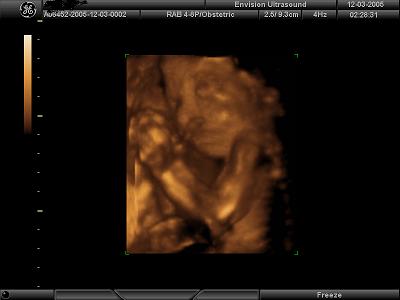

I got great pics at 26 weeks. They say not before 25. Just hit the FAQ section and this website will give you some guidelines..........I attached my 26 week pics so you can get an idea.....

Image Attachment(s):